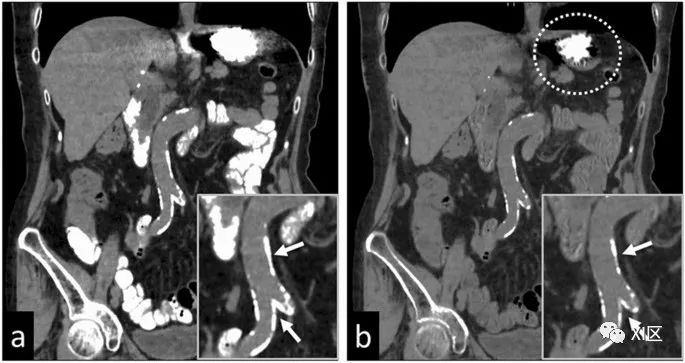

在早期骨折患者中,水肿图有助于识别骨髓水肿(BME)(图18)。通过减少来自骨骼的钙信号,可以创建反映BME的图像。BME图像上的病变清楚地反映了骨髓中的水分含量;这些图像与脂肪抑制的T2加权图像有很高的相关性。在BME图像上诊断早期骨折所需的时间比磁共振成像所需的时间要短。

图18 69岁男性T12和L1椎体上终板压缩性骨折。左:传统CT显示终板区骨髓密度与邻近椎体有明显增高;中:虚拟去钙图像显示与左图相比,椎体骨髓信号有相应改变,另外L4椎体上缘终板有额外信号增高,代表骨挫伤;右图:压脂图像显示T12、L1及L4椎体相应部位骨髓水肿。因此,传统灰阶CT忽略的一个额外新鲜骨折在虚拟去钙图像被正确检测。水肿图